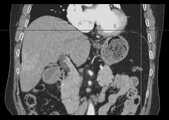

Fig. 8a is a schematic diagram of a sequence of CT images viewed from a transverse direction.

fig. 8a-8c are raw three-dimensional data of sequential CT images viewed from three directions, the transverse, sagittal and coronal planes, respectively. Fig. 9a to 9c are the second binarized images obtained after the method removes the bed plate area, respectively, and it can be seen from fig. 9a to 9c that none of the skin surface contours of the human body area is damaged. Fig. 10a to 10c are respectively third binarized images obtained after filling the cavity by the method, and it can be seen from fig. 10a to 10c that the third binarized images are completely overlapped with the original three-dimensional data of the sequence CT image, and the lung region with a low threshold value is effectively filled. As can be seen from FIGS. 11a-11d, after another serial CT image is reconstructed by the method, the three-dimensional model of the skin can be fused with the third binary image and the serial CT image. And finally mapping the obtained three-dimensional model of the skin back to a 2D mode, and comparing the coincidence degree of the skin boundary in the three-dimensional model of the skin and the binary image to obtain figures 12a-12 c. In addition, the three-dimensional models of the skin of other parts of the human body obtained by the method are shown in figures 13a-13 c.